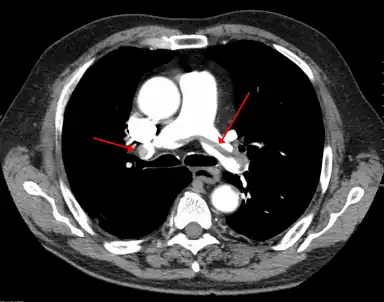

A pulmonary embolism (PE) occurs when a blood clot from a deep vein (a DVT) detaches from a vein (embolizes), travels through the right side of the heart, and becomes lodged as an embolus in a pulmonary artery that supplies deoxygenated blood to the lungs for oxygenation.[28] Up to one-fourth of PE cases are thought to result in sudden death.[12] When not fatal, PE can cause symptoms such as sudden onset shortness of breath or chest pain, coughing up blood (hemoptysis), and fainting (syncope).[29][30] The chest pain can be pleuritic (worsened by deep breaths)[29] and can vary based upon where the embolus is lodged in the lungs. An estimated 30–50% of those with PE have detectable DVT by compression ultrasound.[30]

A CT image with red arrows indicating PE (grey) in the pulmonary arteries (white)